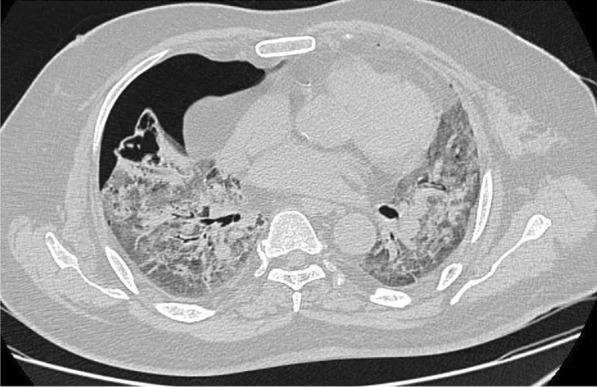

Out of 48 patients who developed barotrauma, 30 (62.5%) presented with pneumothorax, 22 (45.8%) with pneumomediastinum, 10 (20.8%) with subcutaneous emphysema, and 2 (4.1%) with pneumopericardium. Of those that developed barotrauma, 45 (93.7%) patients were in acute respiratory distress syndrome. In patients with and without barotrauma, significant factors were white blood cell count ( = 0.001), neutrophil percentage ( = 0.012), and lymphocyte percentage ( = 0.014). There were no statistically significant differences in CRP, procalcitonin, d-dimer test, LDH, or ferritin.

结果

在48例发生气压伤的患者中,30例(62.5%)出现气胸,22例(45.8%)出现纵隔气肿,10例(20.8%)出现皮下气肿,2例(4.1%)出现心包积气。在发生气压伤的患者中,45例(93.7%)患有急性呼吸窘迫综合征。在有和没有气压伤的患者中,显著因素为白细胞计数(=0.001)、中性粒细胞百分比(=0.012)和淋巴细胞百分比(=0.014)。在C反应蛋白、降钙素原、D-二聚体检测、乳酸脱氢酶或铁蛋白方面无统计学显著差异。